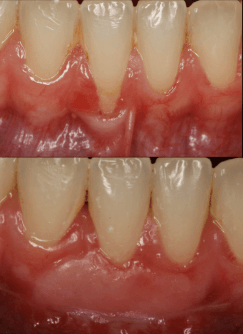

This short quiz will show you images of procedures before and after, and ask you what you’d like to learn. That way, we can send you free trainings that meet you exactly where you are.